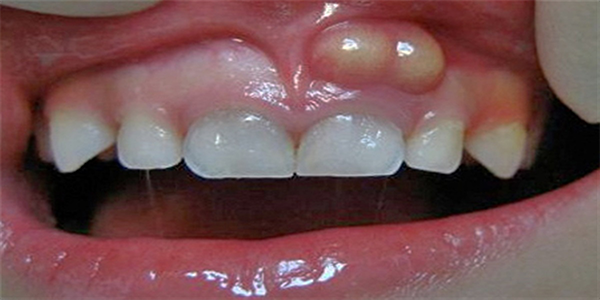

علت ورم لثه چیست؟

یکی از انواع بیماری های لثه ورم لثه انواع مختلفی دارد که به دلایل مختلفی به وجود میاید ولی علت شایع آن، رعایت نکردن بهداشت فردی است. لازم به ذکر است که ورم لثه ناشی از پلاک ممکن است توسط باکتری، ویروس و یا قارچ خاصی ایجاد شود.

علت التهاب لثه تجمع پلاک باکتریهایی بین و اطراف دندانها است که با مرور زمان اگر شخص از مسواک و نخ دندان به طرز درست استفاده نکند، این پلاکها بیشتر شده و در نتیجه منجر به تخریب بافت و ورم لثه میشود. در مراحل شدیدتر ممکن است شخص به طور کلی دندان خود را از دست بدهد.